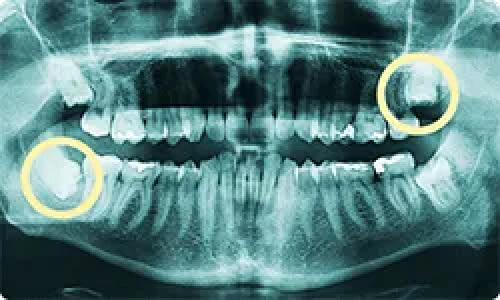

難しい親知らずの抜歯も対応可能 あなたの親知らずはどんな生え方ですか?

親知らずの状態によって、抜歯しなくても良いケースや痛みがなくとも横向きに生えており抜いた方が良いケースなどさまざまです。千賀デンタルには、口腔外科に特化した専門ドクターが常駐しておりますので、年中無休で親知らずの抜歯が可能です。また、他院で断られた難症例のケースでも大学病院へ行かずとも処置が可能ですので、まずは一度ご相談くださいませ。

斜め、真横に生えている

上下の親知らずを抜きたい

親知らずの生え方

埋まっている